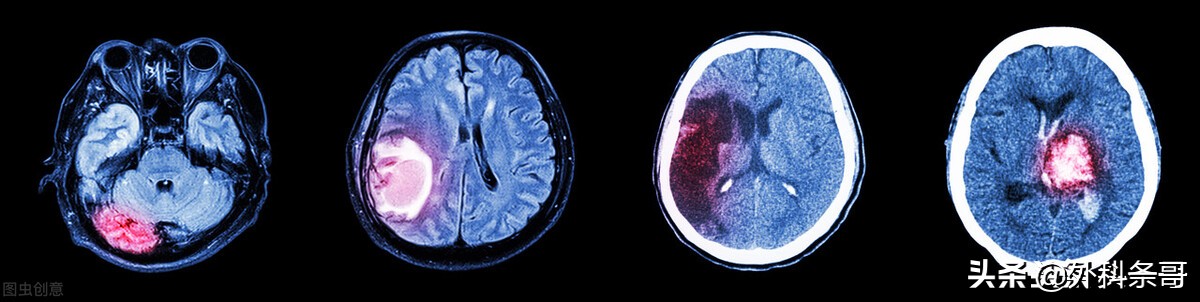

4 CT分型及治疗

考虑到CT影像已较普遍应用,且能早期及时诊断,并可明确血肿的位置及范围,另外,血肿的部位及大小同预后有密切关系,故应用CT进行分型,方便可靠,价值大,被广泛应用于临床。主要是根据出血的部位、血肿大小、破入脑室、累及中线结构的程度,来进行分型,结合脑部受损征象,来选择治疗法。

4.1 壳核出血 为临床最常见类型。CT上可按血肿的范围,破入脑室与否,再分为5个亚型:

治疗方法的选择,上述各型血肿量≤30 mL,脑干池形态正常,采用内科疗法,血肿量≥31 mL,脑干池受压,则需手术治疗。手术方式可按CT分型进行,Ⅰ、Ⅱ多采取钻颅穿刺,Ⅲ、Ⅳ、Ⅴ多数须开颅清除血肿,破入脑室者,有的尚可加脑室引流。

4.2 丘脑出血 CT上显示血肿的范围,有无破入脑室,可分为3个亚型。

血肿小,尤其在10mL以内,无明显症状,采用内科治疗。血肿≥15mL,症状进行性加重,应钻颅穿刺或开颅清除手术,破入脑室者可行脑室引流。血肿≥30mL,脑干无严重受压,则需开颅清除手术。但近年有文献认为,同样出血量,丘脑出血破入脑室反而预后比无破入脑室者好,可能因血液破入脑室可减轻对脑实质的压迫。

4.3 脑叶(皮质下)出血 依据血肿大小和脑室受压情况而定,出血量小于30mL,用内科疗法,31~50mL的,可采取钻颅穿刺,大于50mL,多数须行开颅清除术,尤其是脑室明显受压时,更为适宜。

4.4 小脑出血 因为病变靠近脑干,在出现恶化之前多无明显先兆,为防止突然发生脑疝,大多认为手术是唯一有效的治疗手段,除非临床症状轻,出血量<10mL者可考虑暂时进行内科治疗。伴破入脑室而严重积血者,则需同时脑室引流。

4.5 脑干出血 大多采取内科疗法,有继发脑室积血者,可行脑室引流。随着技术水平提高,有不少手术治疗成功的例子,以血肿>5mL为宜。

在脑出血的急性期,尤其是早期,在临床病理改变中,血肿起主导作用,决定预后的重要因素是血肿的部位、大小以及脑脊液循环受影响的程度,即血肿的类型起关键的作用。因此,分型是早期选择治疗方法的重要依据。